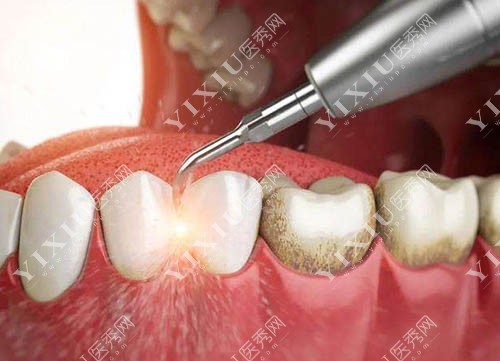

洗牙过程图